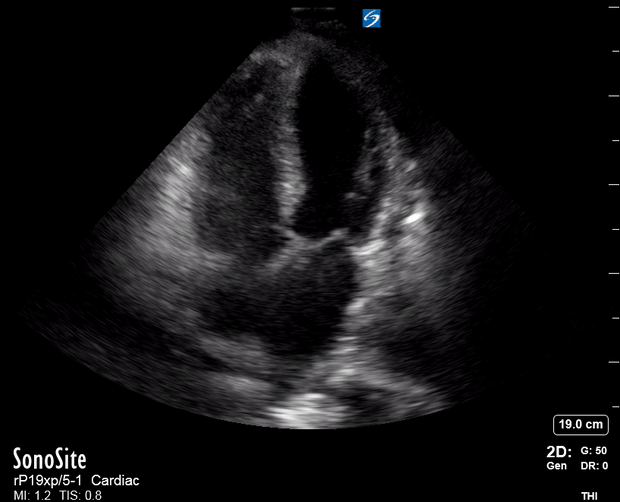

THE VIEWS

The A4C view provides an accurate chamber size comparison. However, achieving a proper A4C view (avoiding foreshortening or ballooning, and visualising the four chambers with a vertically oriented interventricular septum) can be a challenging exercise of image acquisition. Additionally, the PSAX view at the level of the papillary muscles shows both LV and RV side by side and is useful to assess function and size. When RV pressure is high, the septum will be pushed and flattened towards the LV, resulting in the characteristic “D-shaped” LV or “D sign”.

PITFALLS

When comparing size, beware of correct image acquisition, as oblique planes lead to misinterpreting the RV:LV ratio. For apical views be sure to slide the probe sufficiently laterally on the chest wall so that it lies over the true apex. Also, be sure to obtain a real horizontal plane, avoiding foreshortening (ballooning). For the PLAX view it is useful to fan through the heart’s long axis, making sure that LV visualization is maximized relative to the RV. Furthermore, an understanding of probe placement and marker orientation conventions is fundamental. If inadvertently scanning in reverse orientation, the normally larger LV could be mistaken for an abnormally enlarged RV.